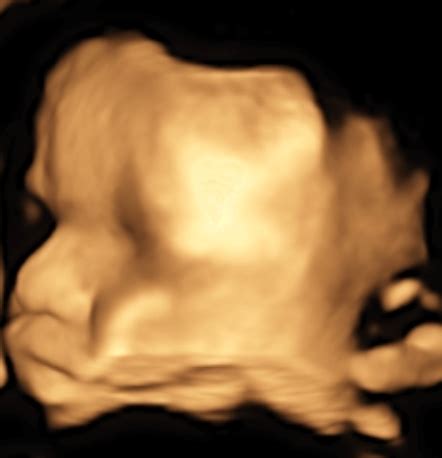

3D a 4D ultrazvuk

Okrem klasického ultrazvuku môžu dnes tehotné ženy absolvovať aj 3D či dokonca 4D ultrazvuk. 3D ultrazvuk znamená, že obraz je spracovaný v troch rovinách a pri 4D ultrazvuku je pridaný navyše aj pohyb. Obľúbenosť 3D a 4D ultrazvuku je práve pre ich lepšie zobrazenie bábätka, vďaka čomu si budúci rodičia môžu lepšie a dôkladnejšie pozrieť svoje bábätko v brušku. Tieto vyšetrenia si ale spravidla tehotné ženy hradia.

Ide o špeciálne zobrazenie bábätka, ktoré vidíte trojrozmerne. Z takéhoto vyšetrenia vám zvyčajne lekár natočí video, na ktorom vidíte aj pohyb dieťatka v reálnom čase. Môžete vidieť, aké má vaše bábätko črty, či dokonca na koho sa podobá. Samozrejme, toto vyšetrenie má svoje limity, nie vždy je úplne zreteľné a vydarené, ale medzi budúcimi mamami je pomerne obľúbené. Lekár vám môže aj vytlačiť 3D fotografiu dieťatka. Takéto ultrazvuky je lepšie robiť až po 18. týždni, aby bolo bábätko dostatočne veľké a aby ste z toho mali dostatočný zážitok. Záznam z neho vám môže lekár poskytnúť na CD, aby ste mali na svojho drobčeka pamiatku, ako vyzeral ešte v brušku.

V súčasnosti už majú budúce mamičky možnosť pozrieť si bábätko na rôznych druhoch ultrazvukov. Poznáme klasické 2D, ale aj 3D a 4D ultrazvuky. Prenatálny ultrazvuk sa robí 2D formou a z lekárskeho hľadiska je smerodatným pre všetky potrebné údaje, ktoré má lekár zistiť o plode. 3D a 4D ultrazvuky slúžia viacmenej pre potešenie mamičiek. Tie zároveň nie sú bezplatné a plánované a mamičky si musia za ne priplatiť. Pri 3D ultrazvuku je vidno plod v 3D zobrazení, pri 4D ultrazvuku vidieť navyše aj pohyb bábätka v reálnom čase.

Medzi 28. - 32. týždňom tehotenstva absolvujete ďalšie ultrazvukové vyšetrenie, pri ktorom sa lekár zameria na to isté, čo počas predchádzajúceho vyšetrenia. Na 3D ultrazvuk sa môžete objednať medzi 12. - 16. a 24. - 29. týždňom tehotenstva, kým je v maternici ešte dosť veľa plodovej vody okolo dieťatka. Na rozdiel od 2D ultrazvuku je 3D detailnejší a bábätko na ňom vidíte ako na naozajstnej fotke. Hoci neslúži prvotne na vyšetrenie - na to je dostačujúci 2D ultrazvuk, dajú sa pri ňom odhaliť prípadné anomálie na povrchu tela, ako napríklad rázštep pery či nádor. Pri 4D ultrazvuku vidíte dieťatko v pohybe.